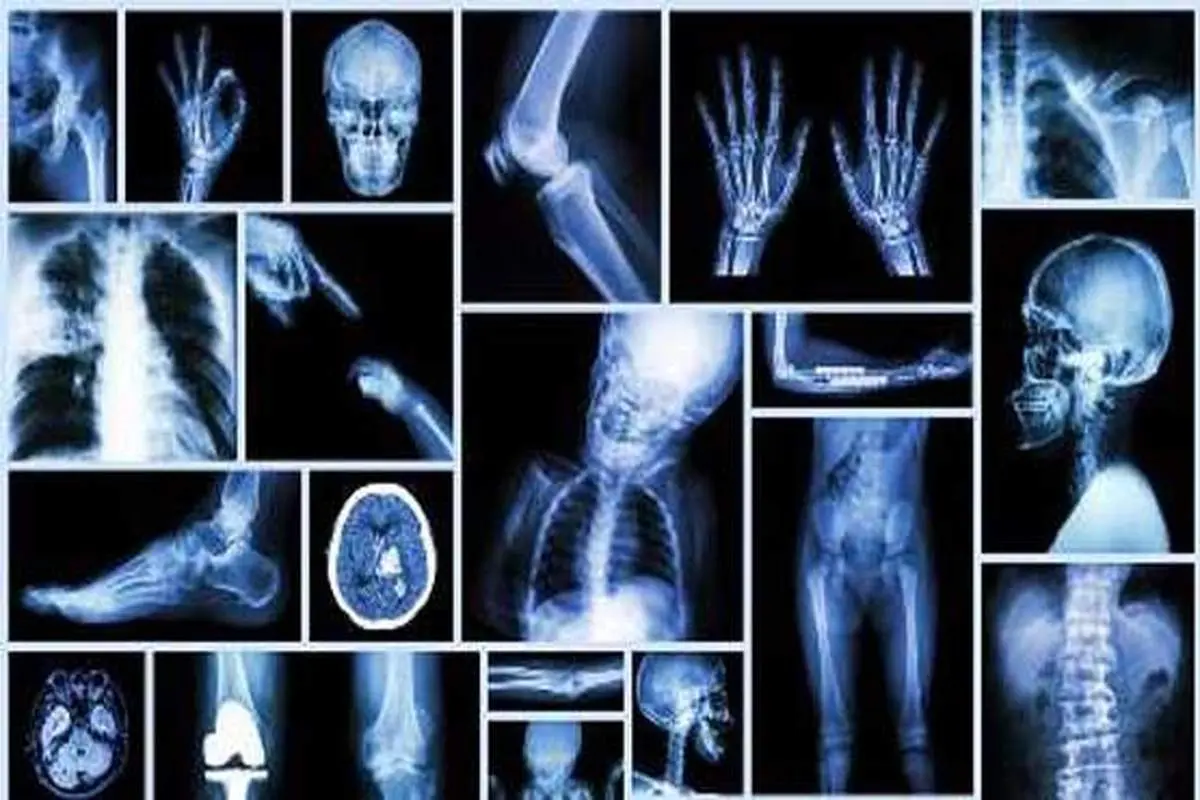

پارسینه: محققان توجه خاصی به چربی موجود در مغز استخوان دارند، زیرا میزان چربی آن با تراکم استخوان ارتباط دارد. در ادامه این مطلب را به نقل از جام جم آنلاین بخوانید.

محققان توجه خاصی به چربی موجود در مغز استخوان دارند، زیرا میزان چربی آن با تراکم استخوان ارتباط دارد. در ادامه این مطلب را به نقل از جام جم آنلاین بخوانید.

با وجود این تاکنون محققان نتوانسته‌اند کاربرد فیزیولوژیکی این چربی را مشخص کنند. اثر فعالیت‌های ورزشی بر چربی بدن بر کسی پوشیده نیست، اما محققان در این مطالعه قصد داشتند علت وجود چربی در مغز استخوان را با کمک فعالیت‌های ورزشی، بهتر درک کنند.

برای این منظور دو گروه از موش‌های آزمایشگاهی را یک ماه پس از تولد، با دو نوع رژیم متفاوت به مدت یک ماه تغذیه کردند. گروه اول دارای رژیم غذایی پرچربی بود که موجب چاقی آن‌ها شد. گروه دوم دارای رژیم عادی بود و موش‌ها تناسب اندام داشتند.

پس از چهار ماه، چرخ‌های گردانی در قفس بعضی از موش‌ها گذاشته شد که موش‌ها درون آن تمرین دویدن می‌کردند.

سپس مغز استخوان تمام موش‌ها را مورد آزمایش و تجزیه و تحلیل قرار دادند و دریافتند میزان و اندازه سلول‌های چربی موجود در مغز استخوان موش‌هایی که فعالیت ورزشی داشتند در مقایسه با سایر موش‌ها به میزان چشمگیری کاهش یافته است.

در واقع این تغییر به حدی بود که میزان چربی موجود در مغز استخوان موش‌های چاق ورزشکار دقیقا مشابه موش‌های لاغر و حتی موش‌های لاغر ورزشکار بود. همچنین استخوان موش‌های ورزشکار ضخامت بیشتری از استخوان‌های سایر موش‌ها داشت.

محققان از این آزمایش‌ها نتیجه گرفتند که چاقی موجب افزایش انباشت چربی در استخوان‌ها می‌شود و این چربی انباشته رفتاری مشابه چربی انباشته در سایر بافت‌های بدن دارد، و در ضمن، ورزش اثرات مشابه با آثار پیش‌گفته در مورد موش‌ها را بر میزان چربی استخوان‌های انسان بر جای می‌گذارد.